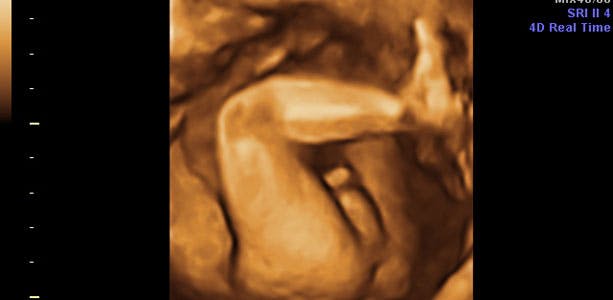

Gravid uge 21: Sure opstød og halsbrand

Den første afføring er begyndt at blive dannet i tarmen, og der er fuld gang i både nyrer og urinveje, som blandt andet har den vigtige funktion at holde fostervandsmængden normal. Barnet synker fostervandet, og nyrerne udskiller det igen. Dette er en af årsagerne til, at jordemoderen i konsultationen kontrollerer mængden af fostervand. I slutningen af ugen måler barnet cirka 22 centimeter og vejer omkring 520 gram. Maveomfanget er næsten 17 centimeter.